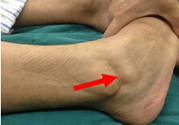

一般來(lái)說(shuō),膝蓋關(guān)節(jié)韌帶斷裂后,會(huì)多多少少的留些后遺癥的。只是看個(gè)人的恢復(fù)情況,會(huì)出現(xiàn)的后遺癥有,如:陰天、下雨、傷處酸痛等癥狀。建議在日常的飲食中要多食用些新鮮的蔬菜和水果,同時(shí)還要經(jīng)常的食用些如牛奶、豆制品之類(lèi)的食物。

韌帶斷裂后,如果不能徹底治愈康復(fù),以后關(guān)節(jié)就會(huì)出現(xiàn)彎曲受限等不適現(xiàn)象,早期一般都會(huì)有僵硬拉扯感、關(guān)節(jié)彎曲活動(dòng)受限制等癥狀。